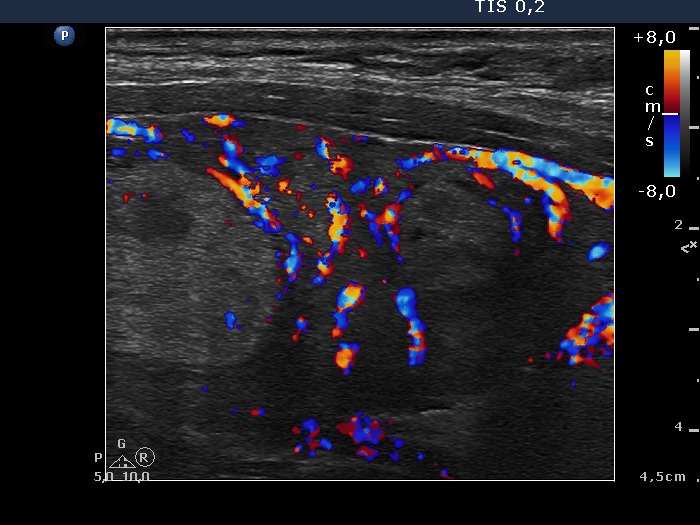

Lower-middle part of the left lobe, longitudinal scan, color Doppler mode.